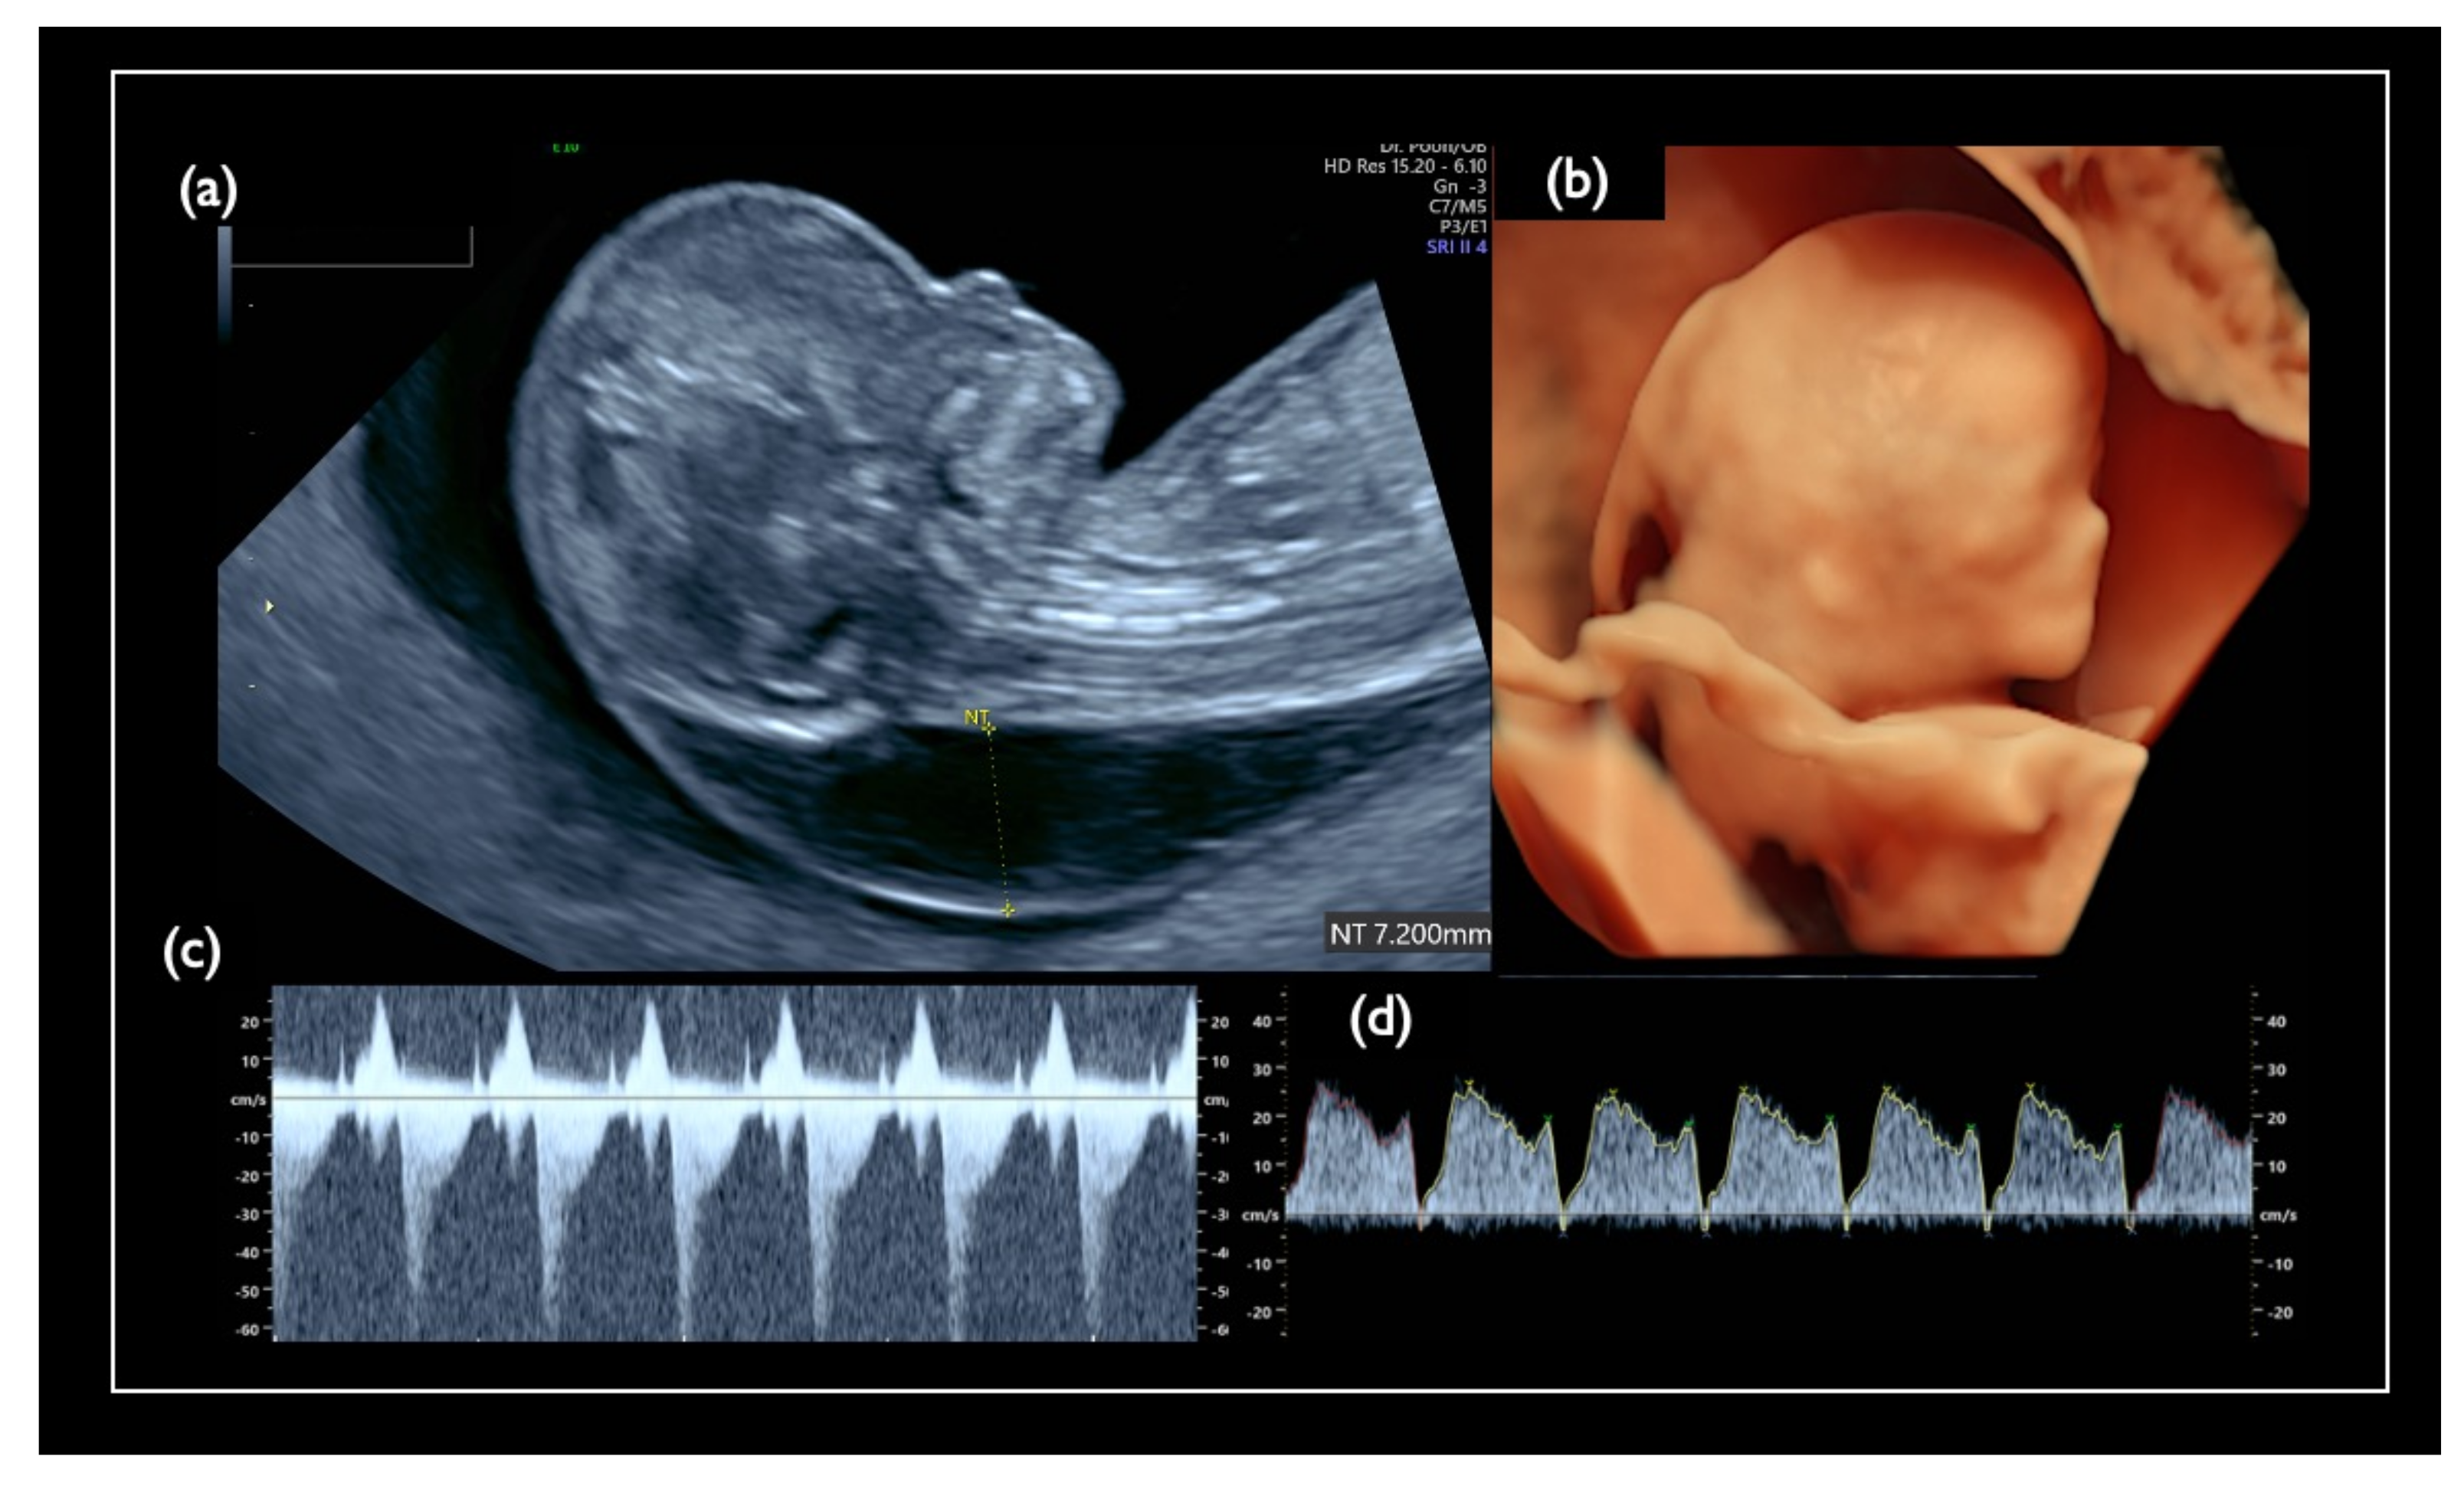

| FN1 | 47,XY,+21 | T21 negative | 1.07 | – | – | – | – | – | – | – | – | 46,XX | unclear | + | 7.2 | Increased NT, GE mild, NB defect, Lowset ear, TR mild, Small stomach, DV reverse, Tachycardia, T21 is strongly suspected |

| Chromosome 18 relevant mosaicism | Mo5 | 13 + 5 | XX,+18 Mosaicism | T18 (56%) | 47,XX,+18/46,XX (44%/56%) | – | – | T18 Negative | 2.09 | + | 8.3 | Increased NT, GE moderate, Small NB, Micrognathia, Lowset ear, T18 like profile, Wrist contracture bilateral, Cardiomegaly, Large VSD, TR severe, MR severe, Stomach invisible, Hyperechoic bowel, DV reversed flow, SUA, Umb.A.reverse, T18 is strongly suspected, |

| NC2 | 12w2d | CVS | 22.8 | 47,XY,+21 | No Call | + | 5.3 | Increased NT, Small CH, GE, bilateral, PE, NB defect, Micrognathia, Lowset ear, s/o Large VSD, TR moderate, Levocardia, RV>LV, Hyperechoic bowel, DV reverse, Short FL, T 21 is strongly suspected |

| NC3 | 13w1d | CVS | 25.8 | 47,XY,+18 | No Call | + | 10.6 | Increased NT, CH, GE, Small NB, Micrognathia, Lowset ear, Hypoplastic ear, Cleft lip (left), Maxillary gap, Mild wrist contracture bilateral, RV>LV, TR, DV reverse, Bradycardia, T18 is strongly suspected |